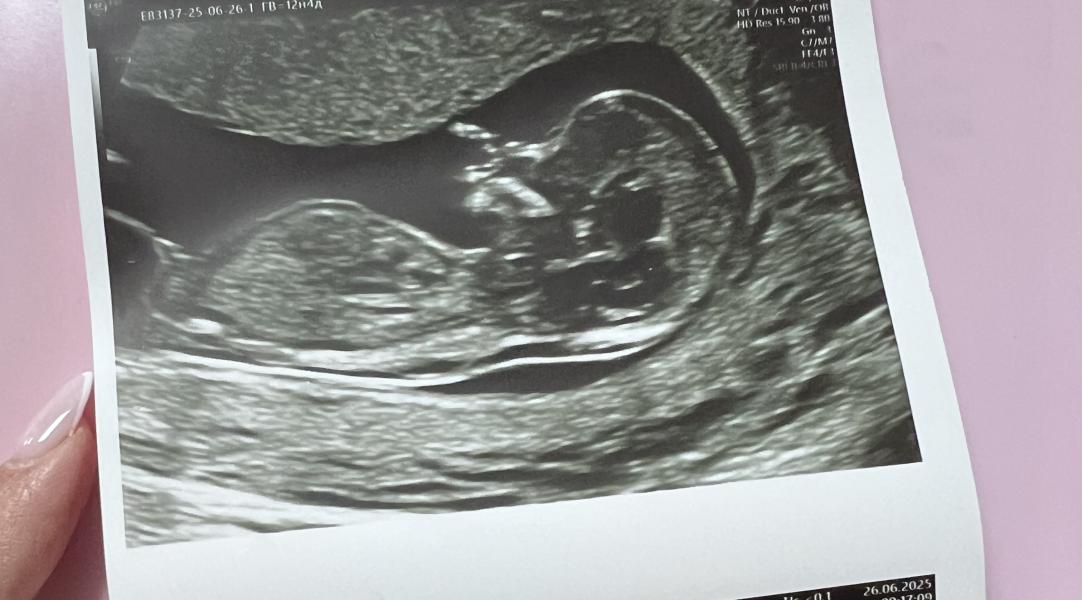

КОНФЛИКТ РЕЗУС ФАКТОРОВ🥲 Сегодня узнала, что у меня 1 отрицательная, а у мужа 1 положительная 🥹 Сегодня был первый скрининг(по УЗИ все хорошо), а по крови результаты через 10 дней. Кто с таким сталкивался? Дождаться результатов или сдать анализ на определение резус фактор малыша? 🥹❤️